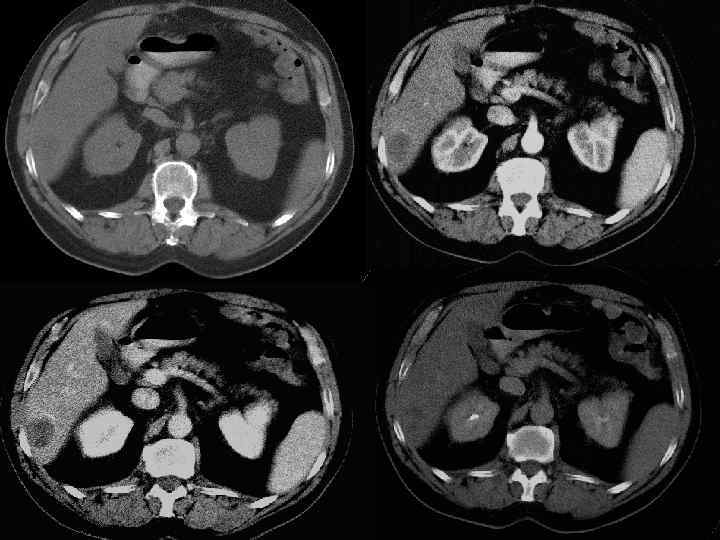

Методы диагностики опухолевой патологии печени. • • • УЗКТ Обследование по органам КТ с контрастированием МРТ с контрастированием Ангиография Пункционная биопсия Опухолевые маркеры (СА-19 -9, РЭА, АФП) Лапароскопия ПЭТ Лапаротомия с удалением опухолевого очага Динамическое наблюдение

Диагностические задачи 1. Являются ли выявленные изменения опухолью? 2. Какова природа опухоли: доброкачественная или злокачественная? 3. Точное указание пораженной доли печени. 4. Точное указание пораженного сегмента печени. 5. Имеется ли поражение ворот печени? 6. Инвазия в окружающие печень структуры. 7. Имеются ли внепеченочные метастазы?